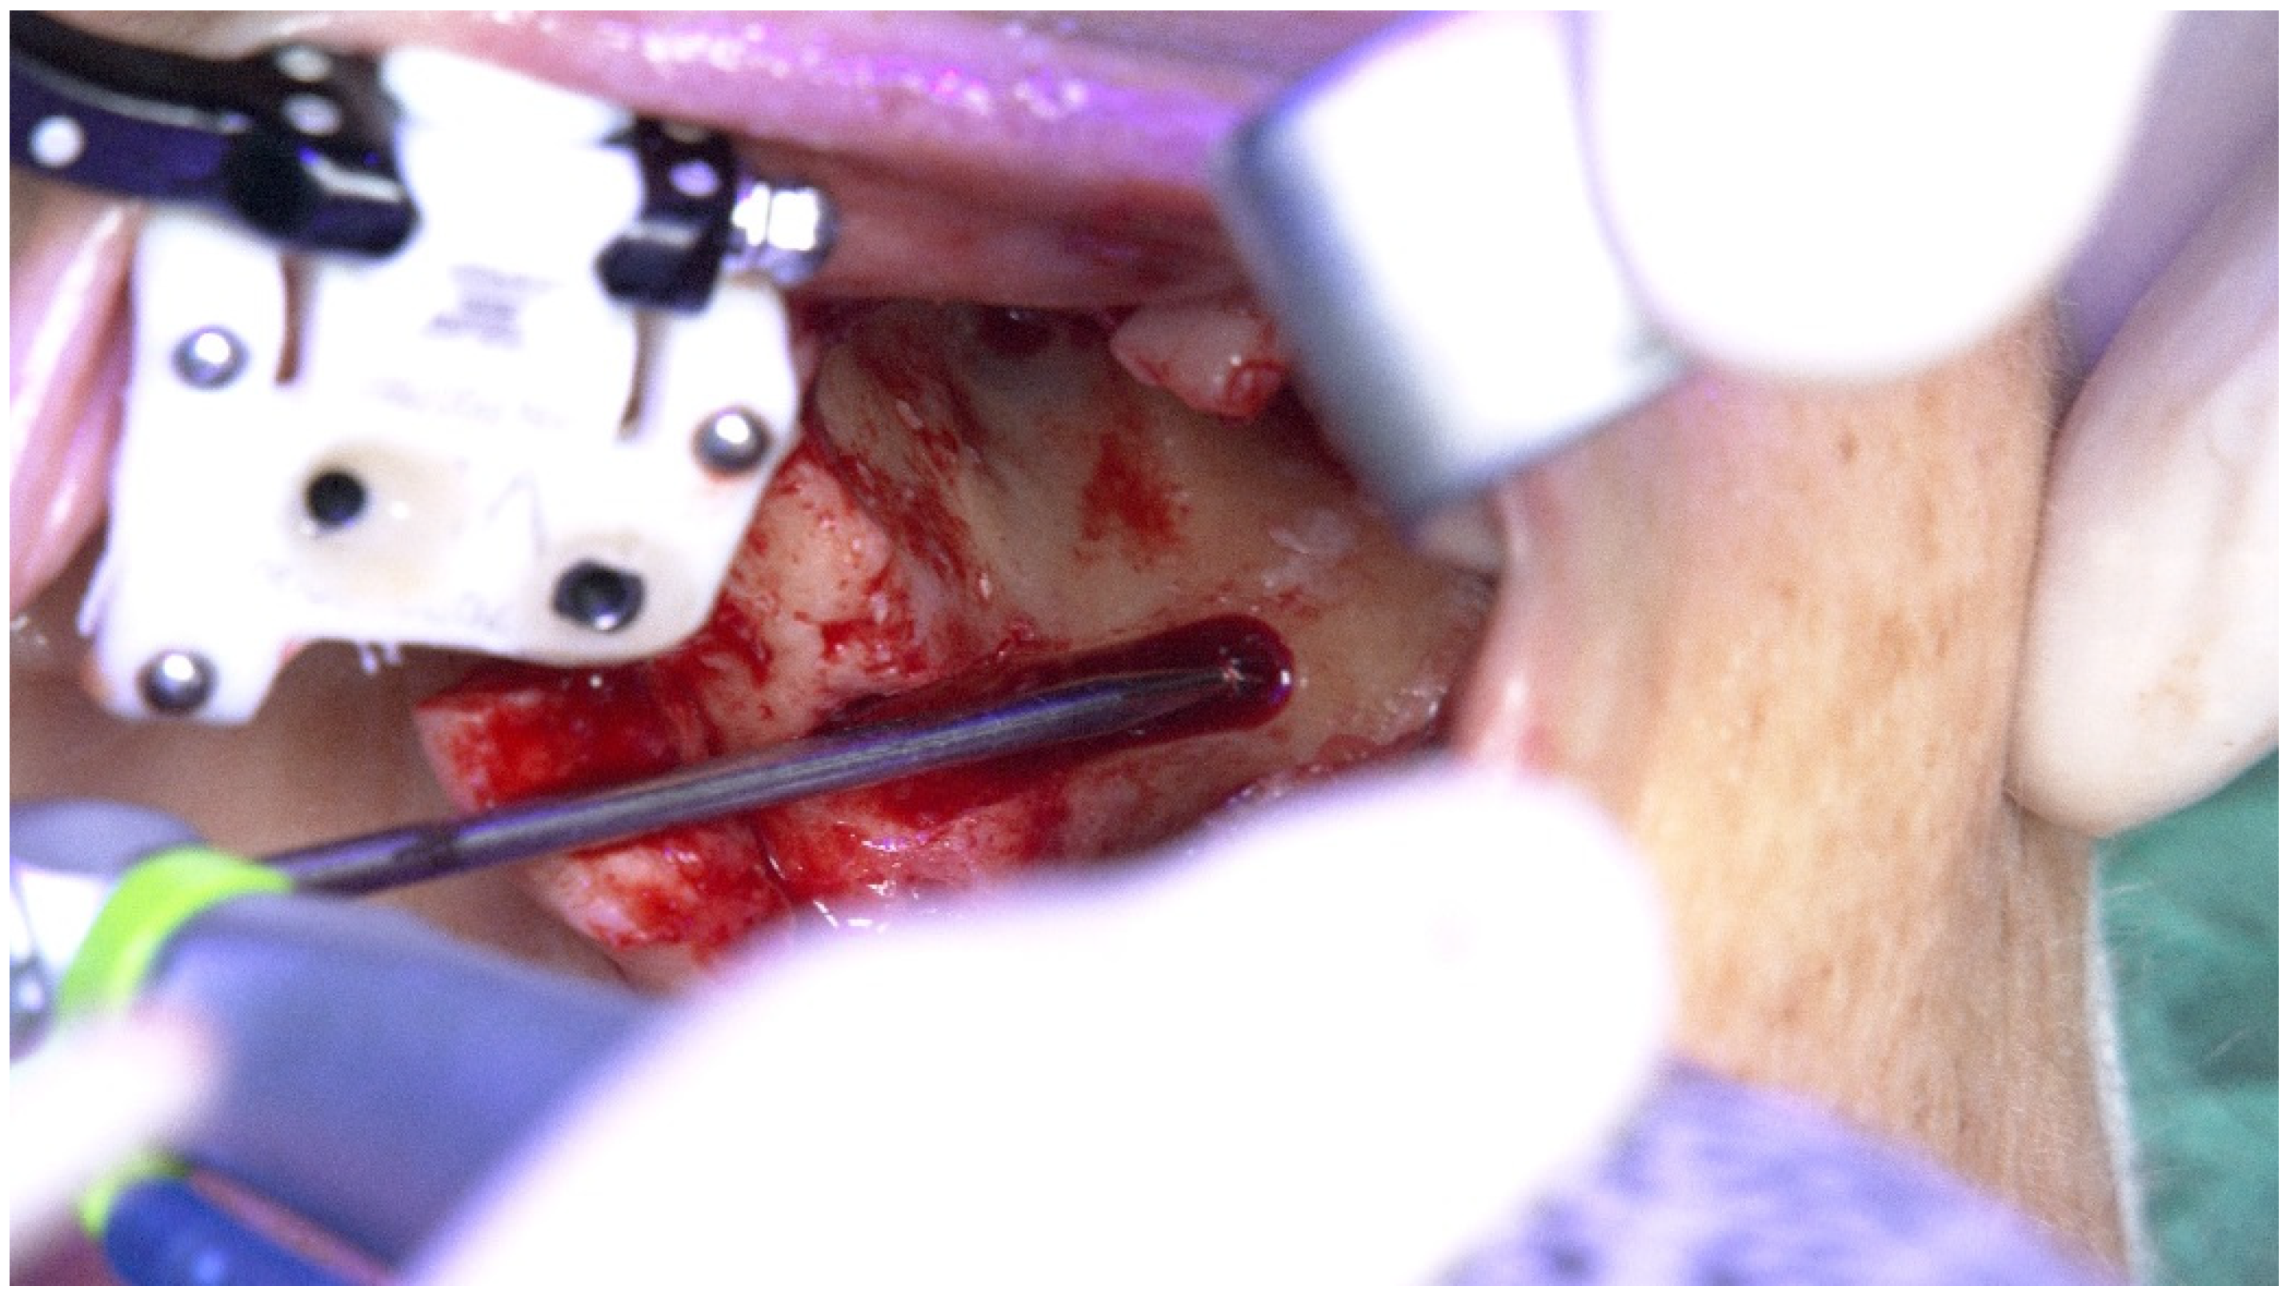

2.1. Patient 1

2.2. Patient 2